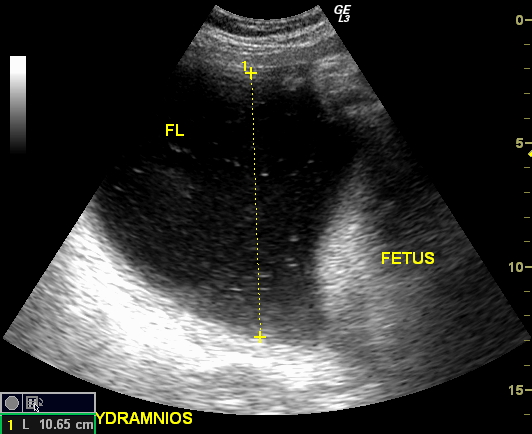

Амнион и Околоплодные Воды: Функции и Роль в Беременности